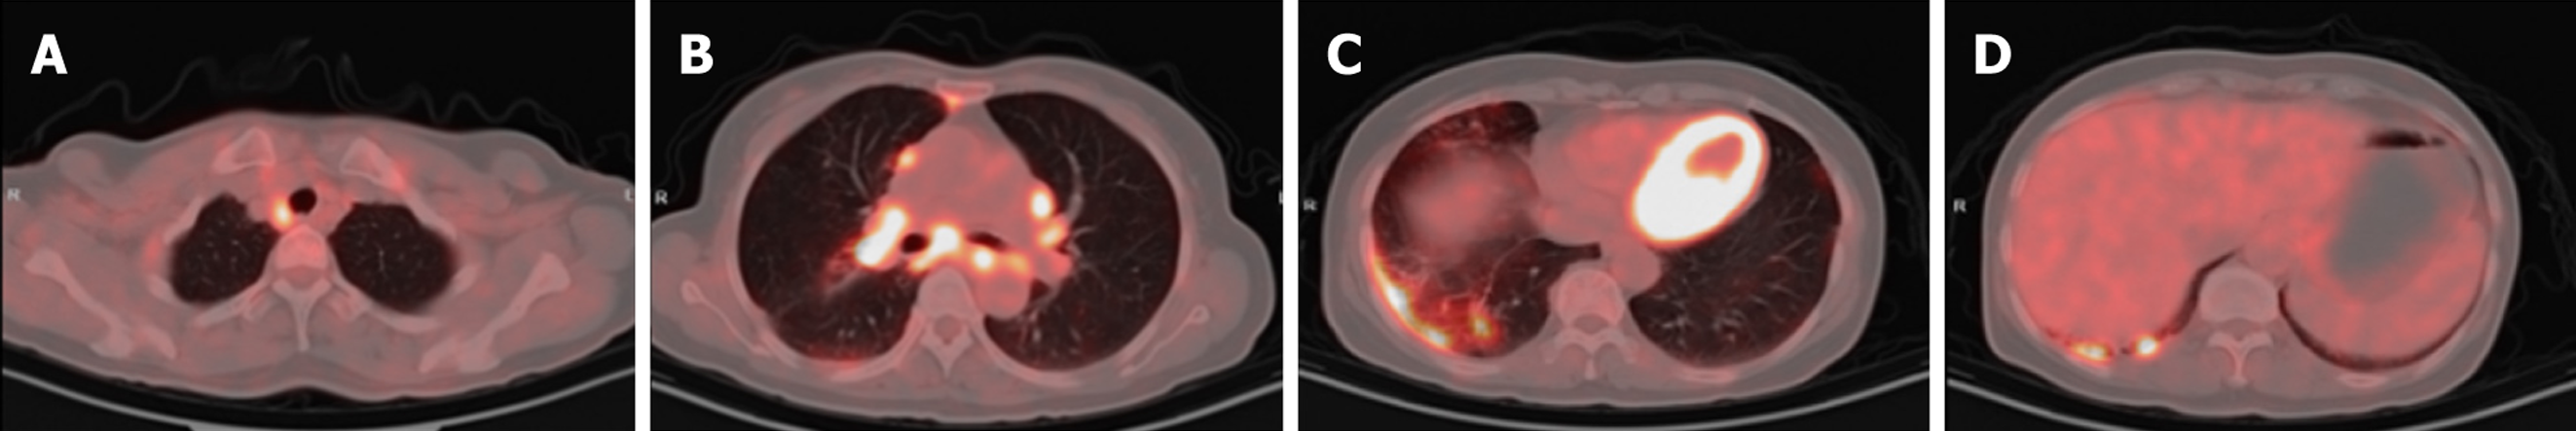

Case 1: A routine chest CT 20 days earlier had revealed a right lung shadow. Subsequent contrast-enhanced chest CT (June 6, 2024) at an external hospital demonstrated a hypervascular right hilar mass with surrounding obstructive pneumonia, scattered enlarged mediastinal lymph nodes, and right pleural effusion. PET-CT suggested malignancy in the right upper lobe with possible pleural involvement, lymphangitic carcinomatosis, and metastases to bilateral hilar/mediastinal lymph nodes (June 17, 2024; Figure 3). In addition, multiple subpleural lung nodules with low metabolic activity were observed. A repeat contrast-enhanced chest CT on June 28, 2024, confirmed a 2.7 cm × 2.0 cm irregular, heterogeneous mass in the right upper lobe, accompanied by obstructive pneumonia and enlarged right hilar and medi

Case 2: Initial contrast-enhanced chest CT at a local hospital revealed multiple enlarged lymph nodes in the right supraclavicular fossa, mediastinum, and bilateral hilar regions (some poorly demarcated from the mid-esophagus), bilateral pulmonary nodules, right bronchial dilation with acute/chronic infection, and localized right pleural thickening (Figure 5). Subsequent PET-CT (December 11, 2024) demonstrated the following symptoms (Figure 6): (1) Widespread hypermetabolic lymphadenopathy (bilateral supraclavicular, mediastinal, hilar, internal mammary, abdominal, and retroperitoneal nodes; SUVmax 8.16; (2) Nasopharyngeal thickening with hypermetabolism; (3) Bilateral hypermetabolic pulmonary consolidations with interstitial changes (prominent in the right upper lobe posterior segment); (4) T11 vertebral focal hypermetabolism (no CT evidence of bone destruction); and (5) Splenomegaly (normal metabolism).